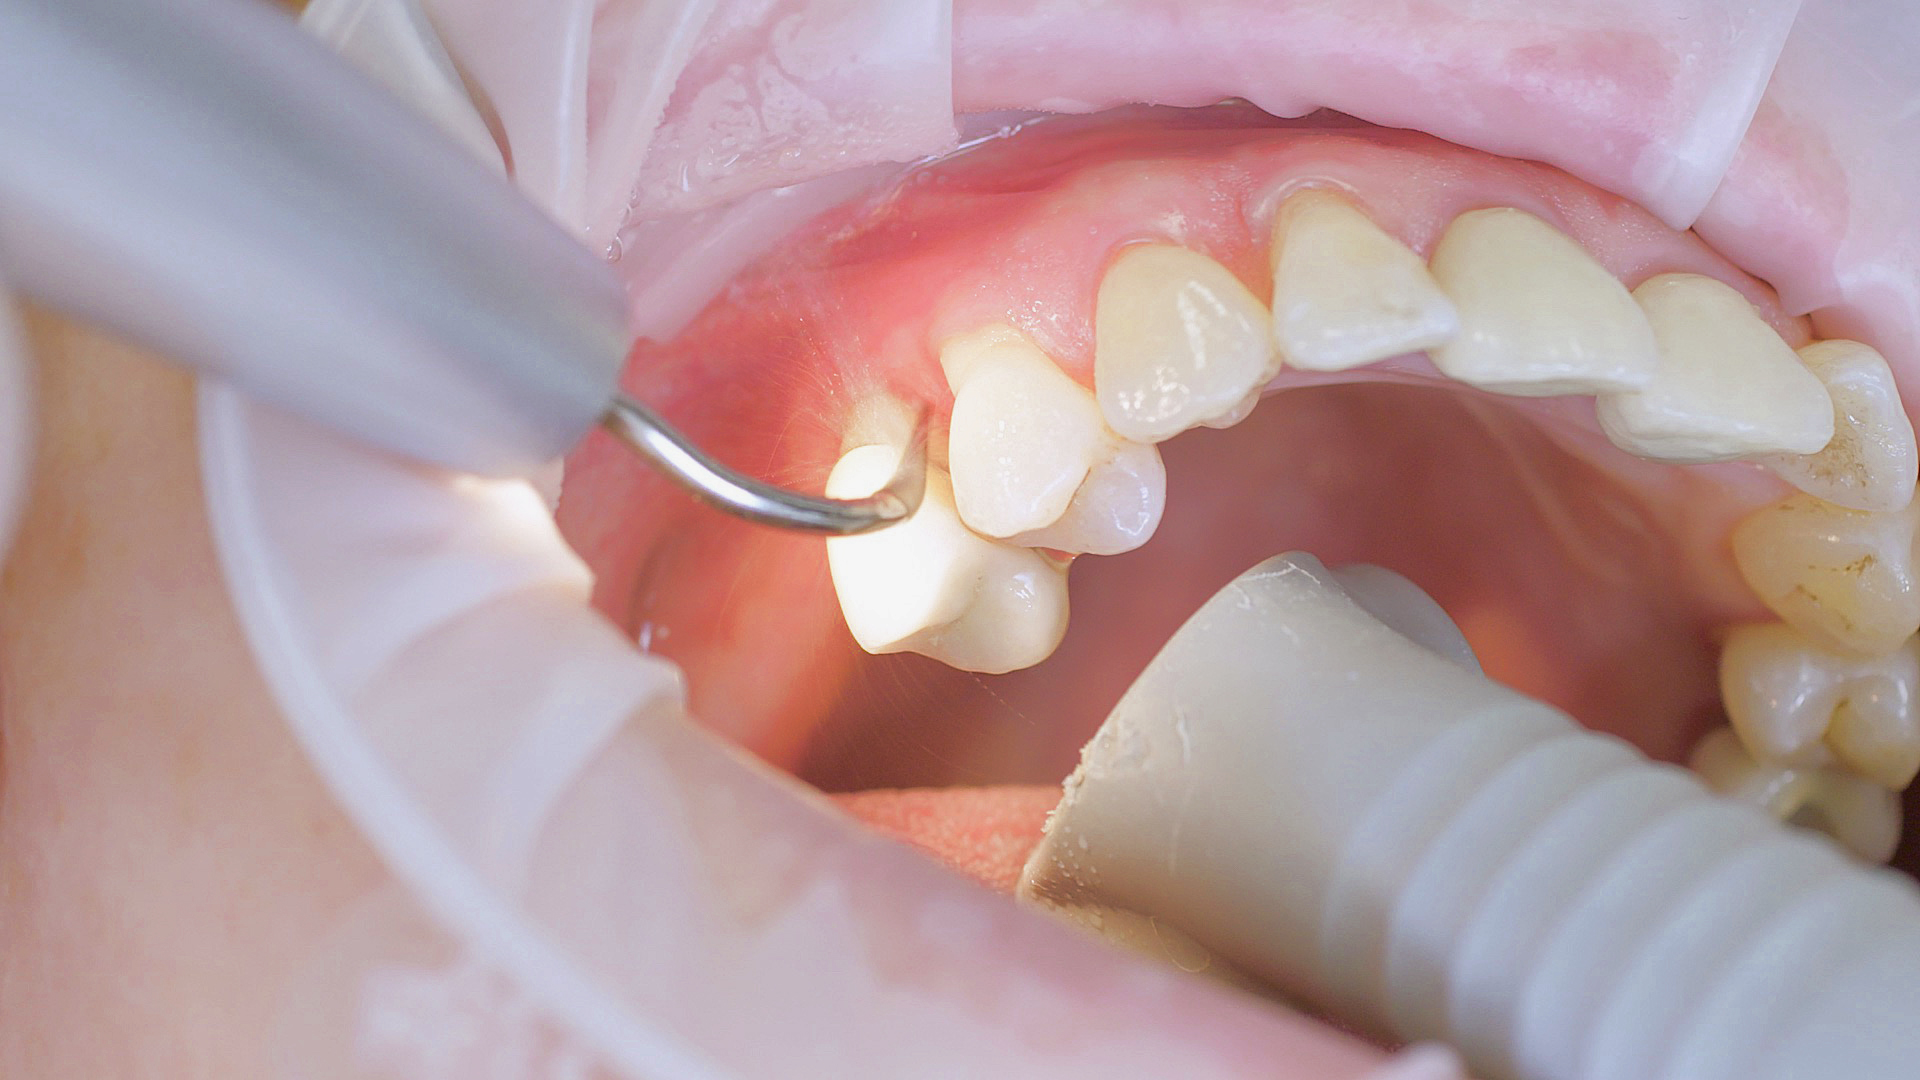

Si nécessaire, un traitement parodontal préventif est effectué. Un nettoyage dentaire professionnel contribue dans un premier temps à des conditions gingivales saines. Il permet d’éliminer le tartre (Fig. 1) et le biofilm (Fig. 2) jusque dans le sulcus gingival. En association à des consignes d’hygiène buccodentaire méticuleuses,

il élimine également à long terme le risque de récidives d'inflammation chez le patient.[15]

Dans le cadre du traitement parodontal préventif, le détartrage subgingival (debridement en anglais) est effectué à l'aide d'appareils à ultrasons et d'inserts paro spécifiques (Fig. 3). Des instruments manuels peuvent également être utilisés. En fonction de la situation, d'autres mesures, y compris chirurgicales et régénératives, peuvent s’avérer nécessaires.